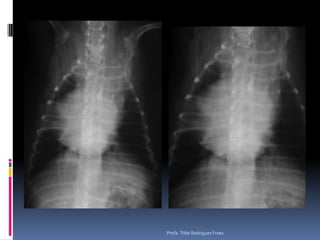

Animal: Dusty, felino, macho, 18 anos, SRDPesquisa de metastasesProfa. Tilde Rodrigues Froes

Exame radiográfico torácicoPesquisa de metástasesDiferentes padrõesIntersticial reticularIntersticial reticulonodularIntersticial nodularAlveolar (quando ?)Áreas cavitárias* Considerar sempre as limitações dessa análise* Em gatos* Efusão pleuralProfa. Tilde Rodrigues Froes

Animal: Dusty, felino,macho, 18 anos, SRDPesquisa de metastasesProfa. Tilde Rodrigues Froes

Exame radiográfico torácicoPesquisade metástasesDiferentes padrõesIntersticial reticularIntersticial reticulonodularIntersticial nodularAlveolar (quando ?)Áreas cavitárias* Considerar sempre as limitações dessa análise* Em gatos* Efusão pleuralProfa. Tilde Rodrigues Froes